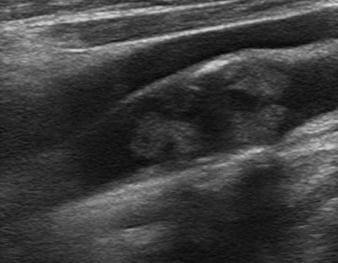

Transcranial Doppler (TCD) and Carotid Duplex Ultrasound (CUS)

Vascular Neurology & Neurovascular Ultrasound